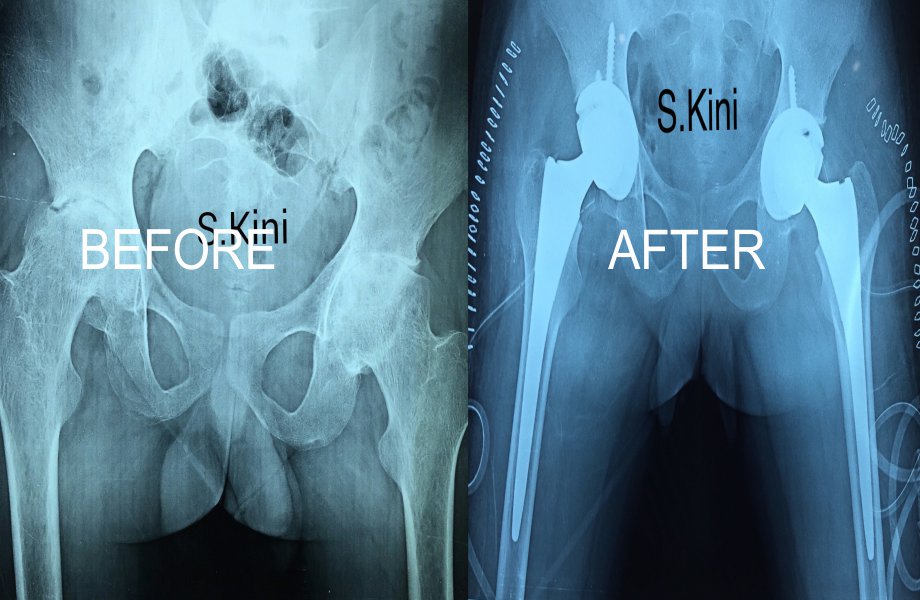

Total Hip Replacement